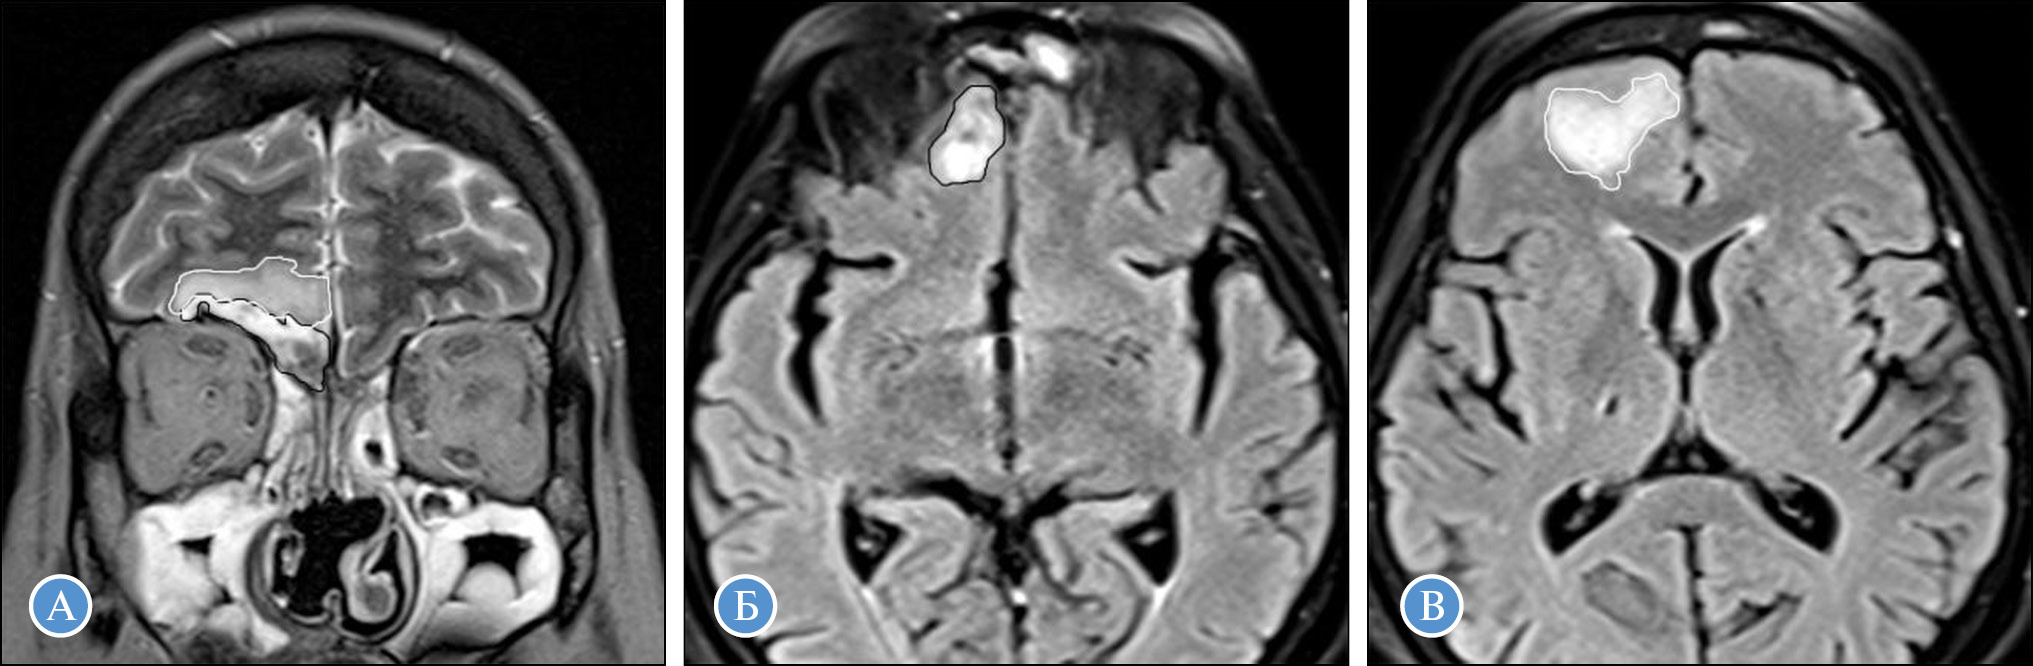

Диагностическая визуализация. Проведенные комплексные исследования с помощью лучевых методов диагностики помогли выявить объем поражения и вовлечения в процесс структур глазницы и головного мозга (рис. 4–6), определить объем хирургического вмешательства и дальнейшую тактику ведения. Лучевые паттерны поражения представлены в табл. 2.

Рис. 6. МРТ головного мозга и околоносовых пазух, корональная плоскость (А), аксиальная плоскость (Б, В): А – Т2-ВИ; Б, В – FLAIR. Отмечается инвазия из пазух носа в полость черепа с вовлечением оболочек и вещества мозга. Зона менингоэнцефалита (черный контур) имеет неоднородный гиперинтенсивный МР-сигнал на Т2-ВИ и FLAIR. По периферии зоны энцефалита определяется отек вещества мозга (белый контур)